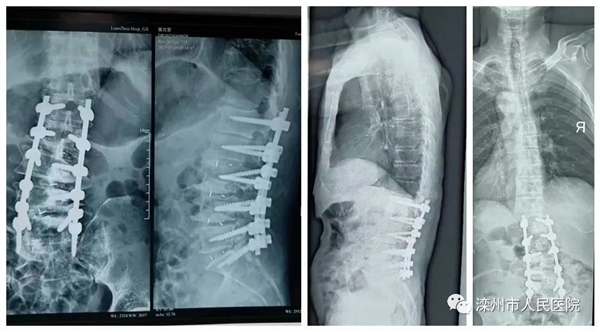

手术前X光片显示脊柱严重侧弯变行

经过精心准备,在天津医院专家的协助下为老人实施手术。手术过程中张景瑜主任医师和李志刚副主任医师精准操作,巧妙实施手术方案,根据脊柱侧弯情况,选择凹侧二级截骨、置入椎间融合器;凸侧进行一级截骨、骨性松解,最大程度纠正脊柱侧弯;同时避免术后产生不良症状,精准植入椎弓根钉,坚强固定,恢复椎体序列。手术历时6个小时圆满完成。

术后X光片